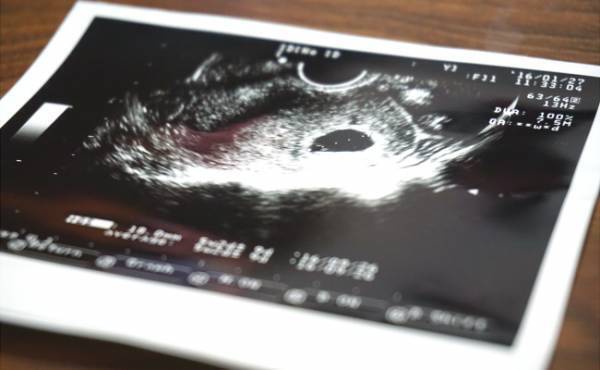

次の通院のために記していた基礎体温がなかなか下がらず、まさかと思って妊娠検査薬を用いてみたところ、なんと陽性! そのときに宿ってくれた赤ちゃんは、結果、私たちの子どもとして生まれてきてくれることになったのです。